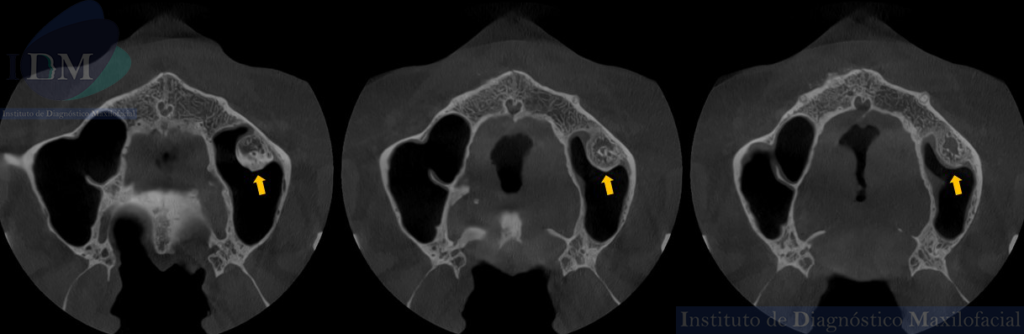

A la evaluación de la tomografía computarizada de haz cónico (TCHC) en los cortes axiales, transaxiales y en la reconstrucción 3D se observa una estructura ovalada hiperdensa heterogénea con contenidos mixtos irregulares localizada en piso del seno maxilar izquierdo con extensión hacia el antro sinusal. Además, en las imágenes tangenciales se observa la presencia de un antrolito adyacente a nivel de la pieza 26.

CORTES AXIALES